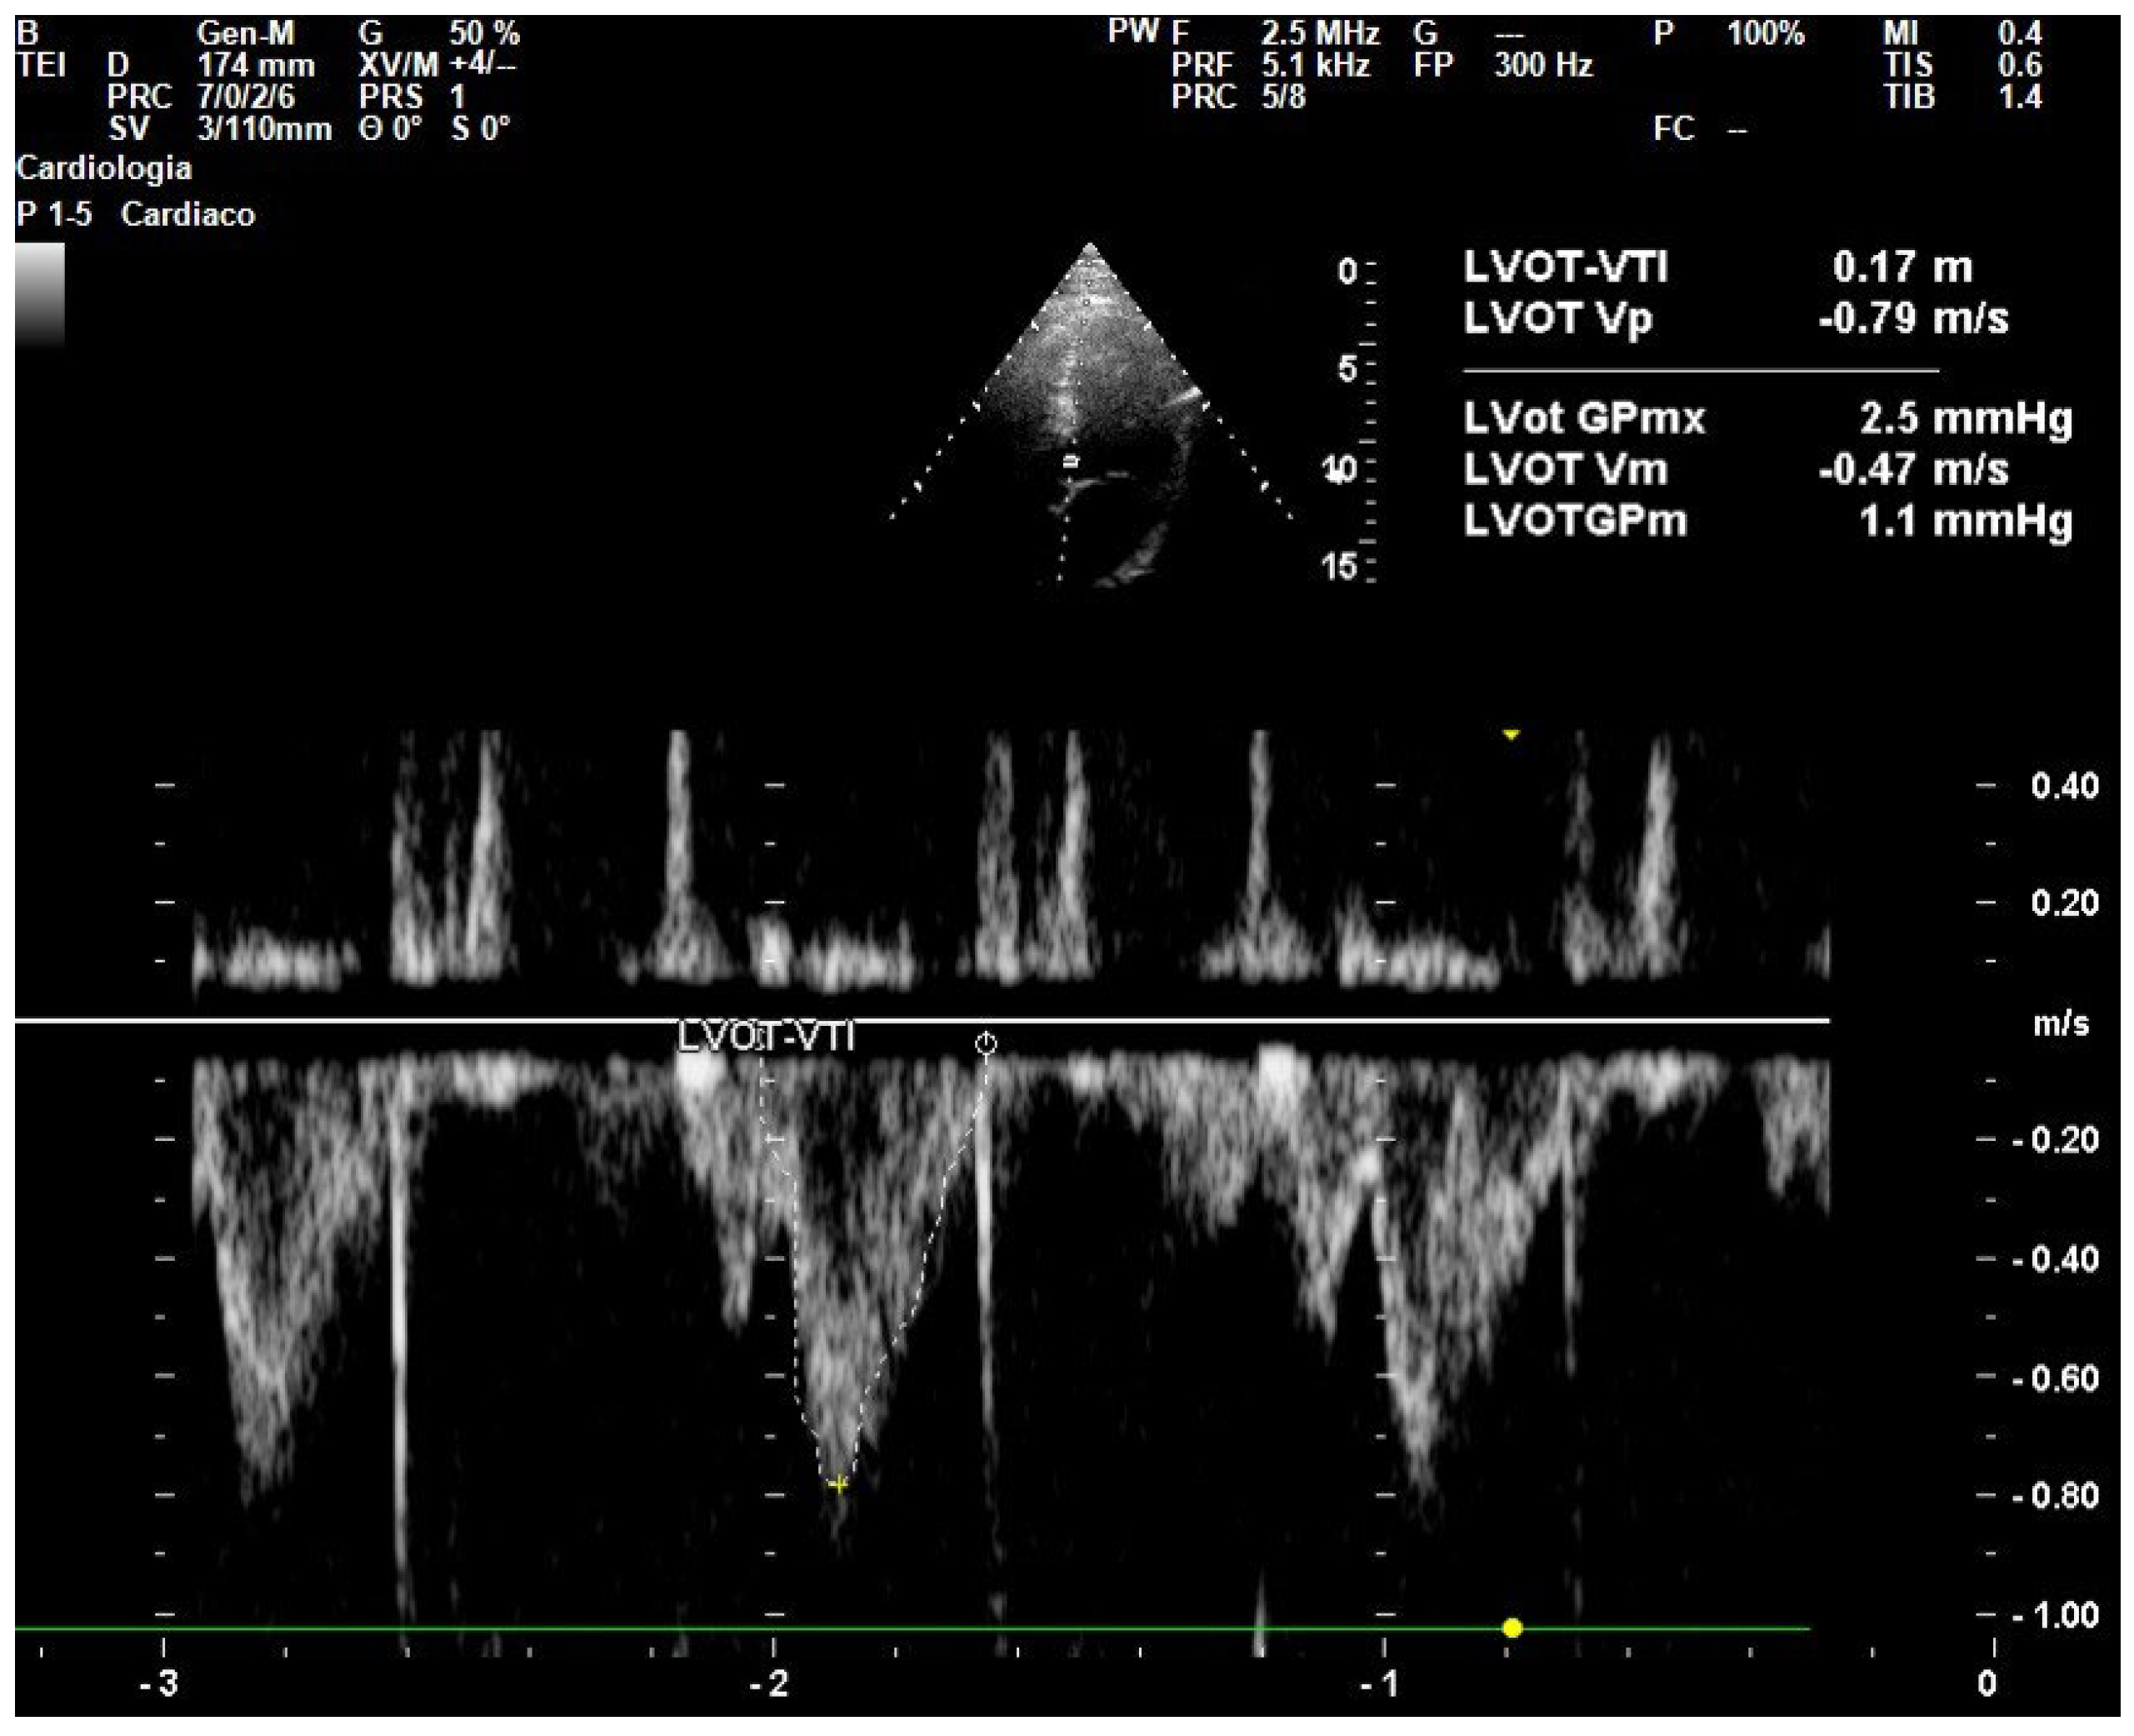

- Wang, J.; Zhou, D.; Gao, Y.; Wu, Z.; Wang, X.; Lv, C. Effect of VTILVOT Variation Rate on the Assessment of Fluid Responsiveness in Septic Shock Patients. Medicine 2020, 99, e22702. [Google Scholar] [CrossRef]

- Dinh, V.A.; Ko, H.S.; Rao, R.; Bansal, R.C.; Smith, D.D.; Kim, T.E.; Nguyen, H.B. Measuring Cardiac Index with a Focused Cardiac Ultrasound Examination in the ED. Am. J. Emerg. Med. 2012, 30, 1845–1851. [Google Scholar] [CrossRef]

- Chanthawatthanarak, S.; Boonasa, K.; Apiratwarakul, K.; Cheung, L.W.; Tiamkao, S.; Ienghong, K. Agreement between Carotid and LVOT Non-Invasive Cardiac Output Measurements in ED Septic Shock Patients: A Prospective Observational Study. Sci. Rep. 2025, 15, 19911. [Google Scholar] [CrossRef]

- Parker, C.W.; Kolimas, A.M.; Kotini-Shah, P. Velocity-Time Integral: A Bedside Echocardiography Technique Finding a Place in the Emergency Department. J. Emerg. Med. 2022, 63, 382–388. [Google Scholar] [CrossRef]